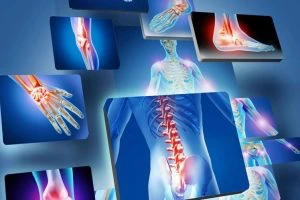

- Artroscopia: accesso mini-invasivo con artroscopio tramite piccole incisioni.

- Artroplastica: sostituzione protesica di un’articolazione.

- Neurolisi / Neurotomia: decompressione o sezione selettiva di un nervo.

- Tenolisi / Tenorrafia: liberazione dei tendini o sutura in caso di lesione.

Chirurgo Ortopedico, laureato in Medicina e Chirurgia e specialista in Ortopedia e Traumatologia. Mi occupo di chirurgia dell’anca e del ginocchio, con ultraspecializzazione nella protesica di primo impianto e di revisione.

Tratto anche chirurgia della mano (neurolisi endoscopica) e spasticità.

Dottore molto disponibile che riesce a metterti a tuo agio. Eseguito intervento al tunnel carpale in endoscopia di entrambe le mani contemporaneamente con buonissimo risultato finale.

Nel frattempo, il dottor Faini mi ha operato entrambe le mani per il tunnel carpale. …. Per farlo, ha usato l’endoscopia (tramite un piccolo foro). In questo modo, la ferita è minima e il recupero è super veloce. Sono riuscito a tornare al lavoro al computer lo stesso giorno …